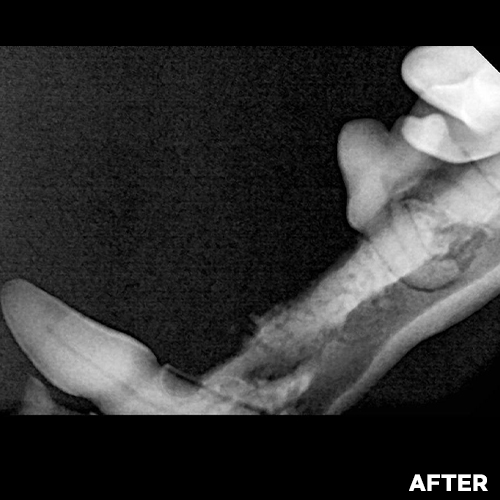

[강아지발치] 잇몸뼈가 녹은 구멍에 자기잇몸뼈가 튼튼하게 재생되어 채워졌어 - 강아지치아발치 2년 후 구강X-ray 비교! -